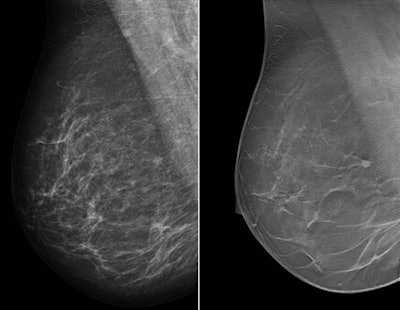

However, this results in increased reading time. Does cutting down to only an MLO view versus an MLO and craniocaudal (CC) view make a difference? That's precisely what Rodriguez-Ruiz and colleagues sought to find out.

They focused specifically on wide-scan angle DBT systems -- those acquiring the projection images over an angular range of 40° to 50° -- because new studies indicate DBT is not inferior to DM even for wide-scan angle DBT systems, eliciting the possibility of using DBT as a standalone modality. Wide-scan angle DBT systems yield improved depth information that better exploits the 3D advantage of DBT over DM, possibly making two breast views unnecessary.

They compared the clinical performance of one-view DBT with three other protocols: one-view DBT (MLO) plus one-view DM (CC), two-view DM, and two-view DM plus two-view DBT. They also evaluated the strengths of one-view DBT as a standalone technique stratified by lesion type, breast density, and radiologist experience.